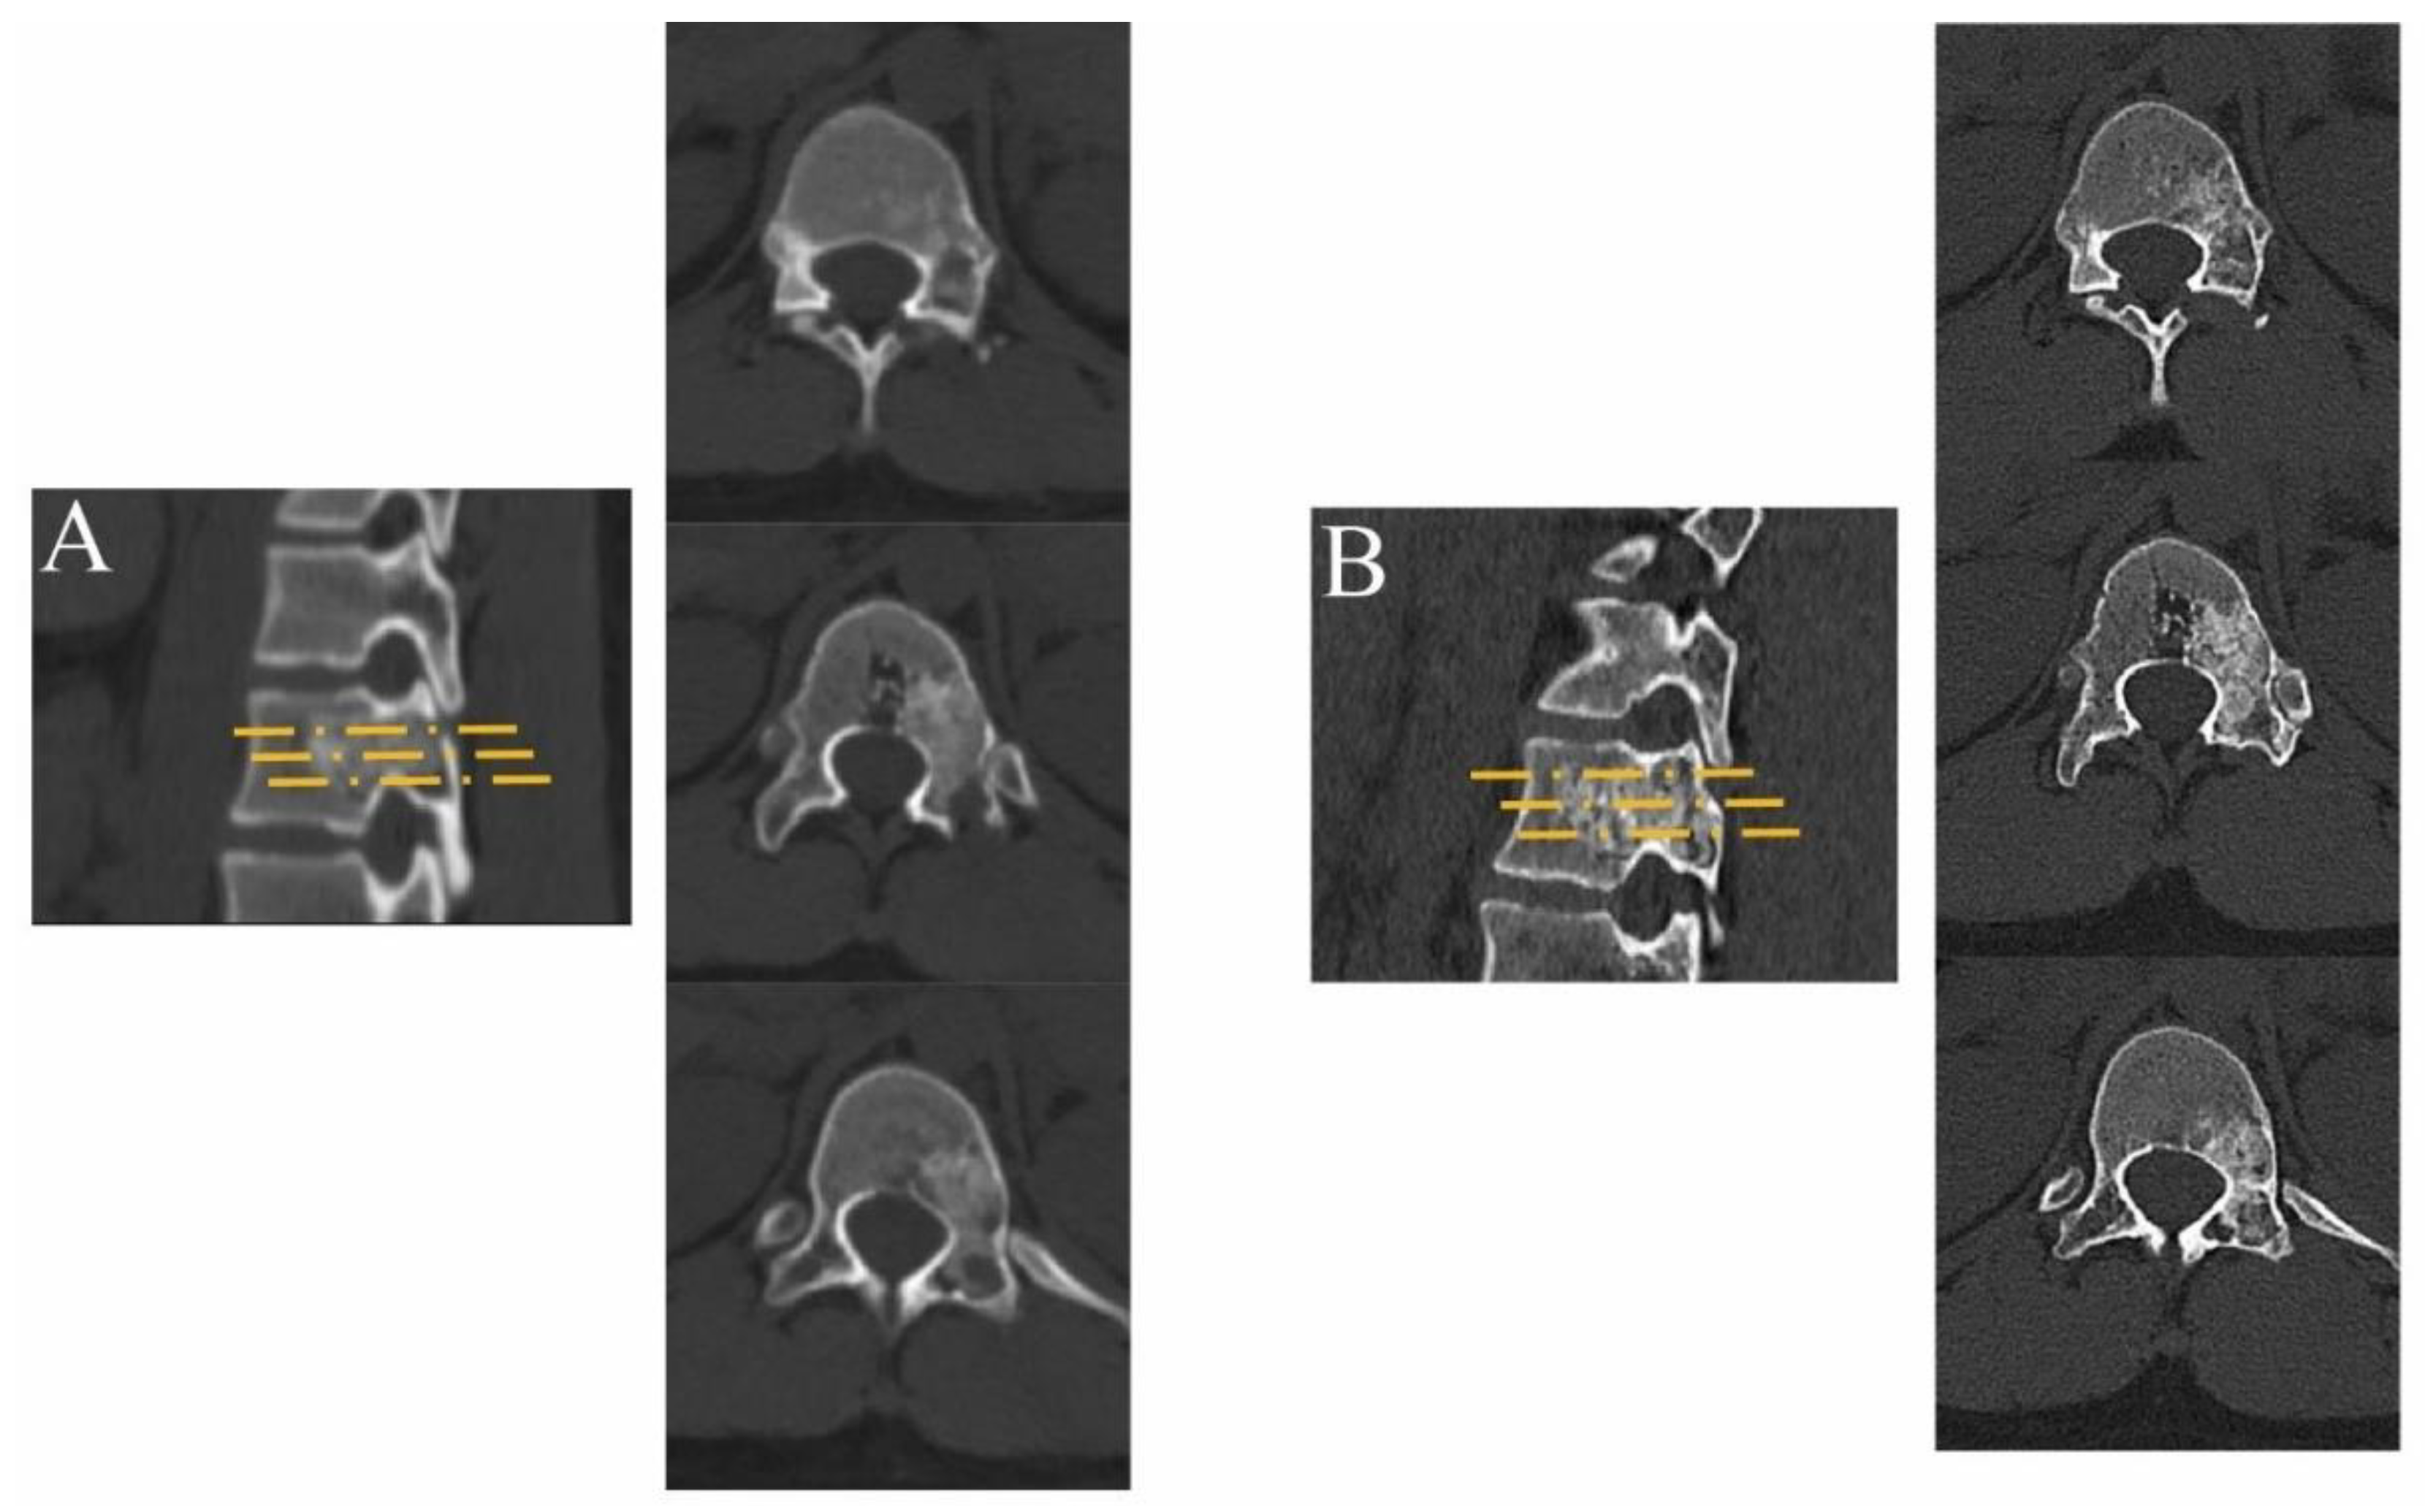

2.2.3. Postoperative Management and Follow-Up

3. Results